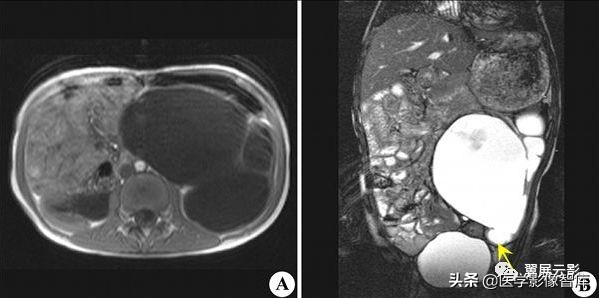

多囊肾

本病常合并多囊肝,此为先天性常染色体显性遗传性疾病,多数学者认为多囊肝是在多囊肾的基础上基因突变的结果,并定位于16号染色体上,也有学者认为该病是由于胚胎发育不良所导致,于胚胎早期管道形成时排列失常,造成无数迷管,于胚胎晚期未退化,且逐渐扩张成囊,成多发性囊肿病,根据发病年龄的不同,将其分为儿童型和成人型,本病多发生于双侧肾脏,可继发感染,结石以及囊内出血和囊壁钙化,也可以恶变,并有阻塞性黄疸及合并皮下囊肿的报道,临床上早期无症状,就诊时肾脏功能已经不同程度受损,肝功能受损程度较轻。

MRI表现为双肾增大和分叶状轮廓,多发囊肿多数为长T1长T2信号,出血性囊肿可为短T1长T2信号或长T1短T2信号,增强扫描所有病灶均不强化,应同时观察合并的多囊肝及胰脾多发囊肿。